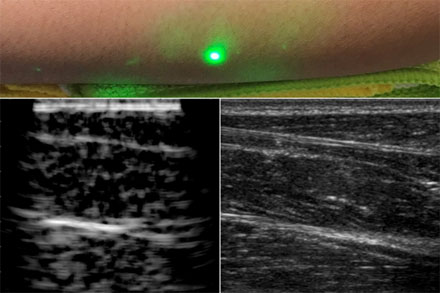

一種新的超聲波技術(shù)利用激光在皮膚下產(chǎn)生圖像,而不像傳統(tǒng)的超聲波探頭那樣與皮膚接觸。新的激光超聲技術(shù)被用來(lái)產(chǎn)生一個(gè)人類(lèi)前臂的圖像(左),這也是使用常規(guī)超聲成像(右)。由X.Zhang等人提供。

最后,研究小組利用麻省理工學(xué)院人類(lèi)實(shí)驗(yàn)委員會(huì)批準(zhǔn)的方案,在人類(lèi)身上進(jìn)行了第一次激光超聲實(shí)驗(yàn)。在掃描了幾名健康志愿者的前臂后,研究人員制作了他們認(rèn)為是第一幅完全非接觸式的人體激光超聲圖像。脂肪、肌肉和組織邊界清晰可見(jiàn),可與使用商用接觸式超聲探頭生成的圖像相媲美。